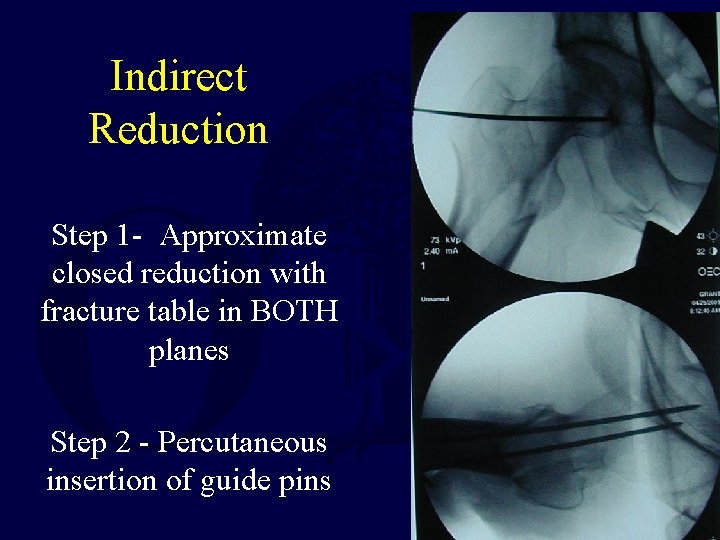

Indirect Reduction: Technique

Indirect Reduction Step 1 - Approximate closed reduction with fracture table in BOTH planes Step 2 - Percutaneous insertion of guide pins